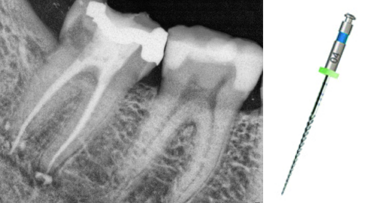

Twenty days later, tooth #48 was restored and I was pleased to find the patient’s cleaning had clearly been consistent and diligent. The improvement was extremely impressive and exceeded my expectations. A fine scaling was carried out with further encouragement to maintain this level of home care.

Two weeks later, the colour and contour of the patient’s gingival margins were as healthy as could be considering the crowding of the teeth. We discussed what treatment with ClearSmile Aligners would involve, such as interproximal reduction (IPR), compliance and risks, and a referral for specialist orthodontics was offered. Preferring to proceed with clear aligners, the patient signed off his full consent, and a two-stage putty impression was taken using a separation wafer. The Archwize digital planning software was used to predict tooth movement and necessary IPR throughout treatment. It suggested that 18 maxillary aligners would be needed.